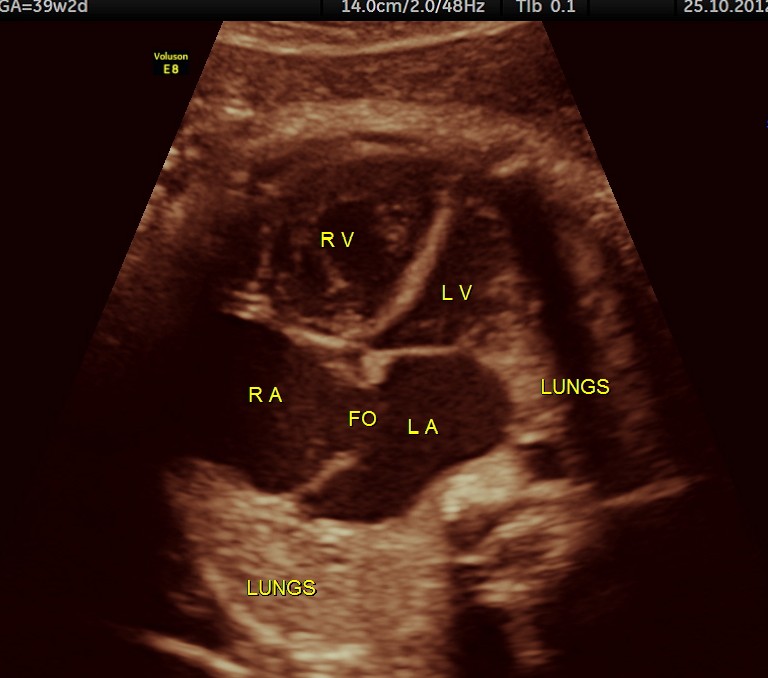

THIS FETUS HAD SEVERE FETAL ANEMIA WITH CARDIAC FAILURE LEADING TO CARDIOMEGALY WITH MITRAL, TRICUSPID AND PULMONARY REGURGITATION .NO OTHER OBVIOUS CARDIAC ANOMALY WAS MADE OUT . THE VENO ATRIAL , ATRIO VENTRICULAR AND VENTRICULO ARTERIAL CONCORDANCE APPEARED TO BE NORMAL; NO SEPTAL DEFECT WAS MADE OUT.